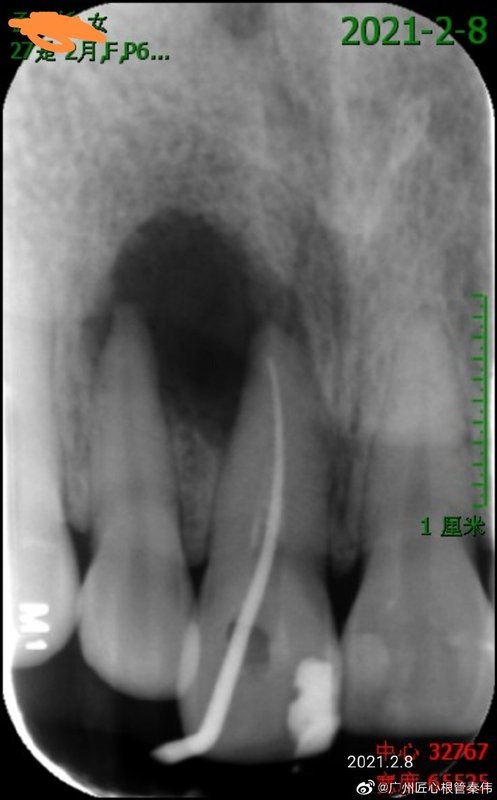

該患者為番禺區(qū)人民醫(yī)院醫(yī)生,外院轉(zhuǎn)診廣州光華口腔,要求右上1,2根管后行根尖手術(shù),來(lái)我院就診后僅僅只對(duì)右上1行根管治療,5個(gè)月后復(fù)查,根尖囊腫基本治愈,治療體會(huì):沒(méi)有聽(tīng)從外院建議對(duì)右2直接做根管(右上2健康不需要根管),這種類型病例很多情況下右上2會(huì)被誤殺行根管治療,不用手術(shù),所有費(fèi)用只花了1500以內(nèi)解決問(wèn)題,根管治療一定要找有經(jīng)驗(yàn)的牙醫(yī)治療,以后會(huì)減少很多坑